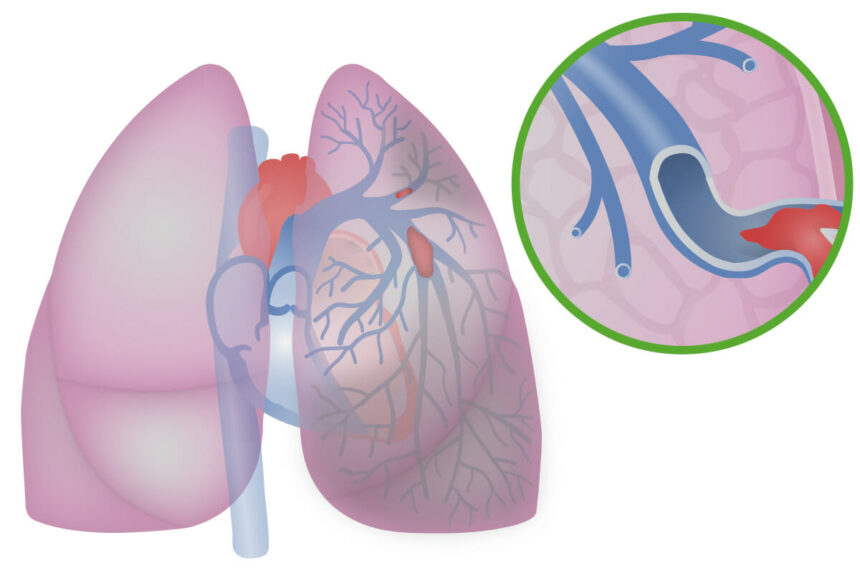

O Tromboembolismo Pulmonar (TEP) é uma condição grave caracterizada pela obstrução de uma parte das artérias pulmonares por um coágulo de sangue. Este coágulo geralmente se desloca de outra parte do corpo, sendo as pernas o local mais comum.

O TEP impede o processo fundamental de oxigenação do sangue:

- O coração bombeia sangue pobre em oxigênio para os pulmões.

- Devido à obstrução do coágulo, esse sangue não consegue chegar para ser oxigenado.

- A obstrução leva a um aumento da pressão sanguínea (hipertensão pulmonar).

- O aumento da pressão sobrecarrega e enfraquece o ventrículo direito do coração.

- Consequentemente, órgãos e tecidos vitais não recebem o sangue oxigenado necessário para funcionar corretamente.